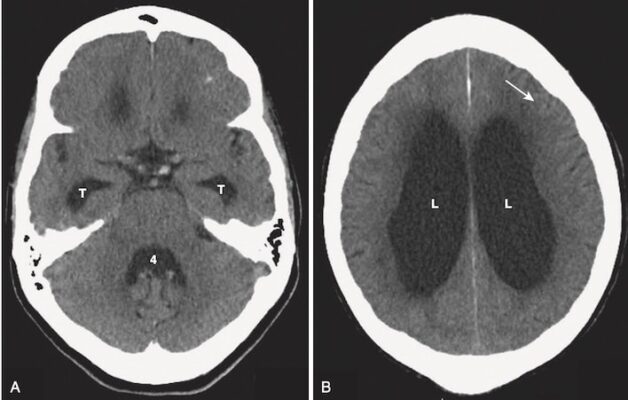

A, Vào khoảng 24 giờ, tổn thương có viền bao quanh tương đối rõ (mũi tên màu trắng đặc) với hiệu ứng choán chỗ biểu hiện bằng sự đẩy lệch của não thất (mũi tên màu trắng chấm), đạt đỉnh điểm từ 3 đến 5 ngày và biến mất sau khoảng 2 đến 4 tuần.

B, Khi đột quỵ trưởng thành, nó mất hiệu ứng choán chỗ, có xu hướng trở thành một tổn thương giảm tín hiệu bờ thậm chí còn rõ nét hơn (mũi tên màu trắng đặc), và có thể kết hợp với giãn não thất kế cận (V) do mất chất não trong vùng bị nhồi máu.